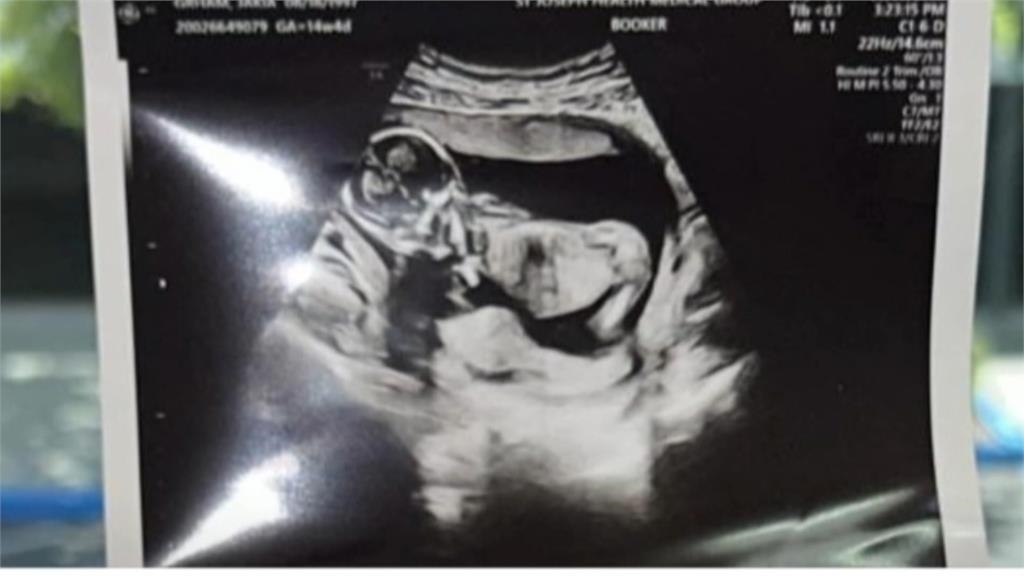

生活中心/馬聖傑、黃柏榕 台北報導目前在台躥禁止代理孕母,但日前有對同志情侶,在社群分享,自己在墨西哥,找了兩個代理孕母,生下四胞胎的故事,引發網友炸鍋!波還沒平息,又有名慈濟醫院的吳姓骨科醫師,po出代理孕母完整生產影片,被砲轟跟拍動物生產畫面一樣!代理孕母議題,再度浮上檯面,衛福部表示,持保留態度。

目前在台躥禁止代理孕母,但日前有對同志情侶,在社群分享,自己在墨西哥,找了兩個代理孕母,生下四胞胎的故事,引發網友炸鍋!波還沒平息,又有名慈濟醫院的吳姓骨科醫師,po出代理孕母完整生產影片,被砲轟跟拍動物生產畫面一樣!代理孕母議題,再度浮上檯面,衛福部表示,持保留態度。

一對完全沒有生育經驗的同志網紅,高調分享在墨西哥找了兩個代理孕母,各生下一對雙胞胎。本來當作一段溫馨故事,卻在網路引起論戰!網友批評忽視代理孕母付出,質疑買小孩賺流量。

在國內代理孕母至今仍不合法,話題還在燒,沒想到又有人上傳代理孕母無碼分娩影片被炎上!

Po影片的男子被起底,還是骨科醫師。他聲稱影片都有經過孕母同意,說自己基因不是特別好,只是個愛孩子的普通人。卻自曝醫生曾建議幫寶寶檢查,被他回絕,認為產檢都正常,有什麼好做的?網友開轟,無法想像是何等的自大與高傲,才會找代孕還把孕母分娩的影片發出來、跟拍動物生產畫面一樣。院方則說,這是醫師私領域個人行為,要他妥善面對與處理。